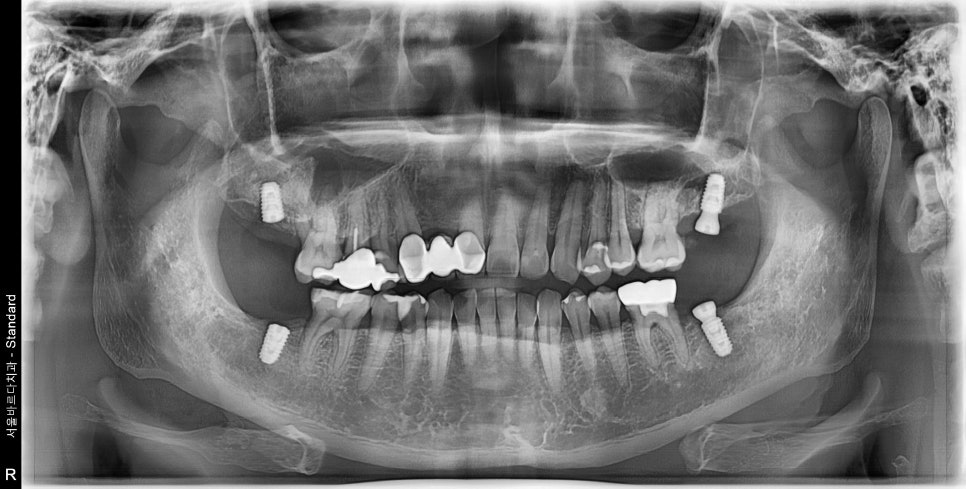

내원 당시의 사진입니다.

실제로 환자분께서는 왼쪽뿐만이 아닌

치주염으로 인해 전체적으로 골소실이 진행된 상태였습니다.

환자분께서 불편해 하시는 왼쪽 위, 아래로

표시해둔 부분처럼 수평적 및 수직적으로

골소실 되어있음을 확인 할 수 있었습니다.

제가 동그라미 친 곳을 보시면 치아 주변에 까만 양상이 보입니다.

염증에 의해 잇몸이 소실되어 방사선 투과성이 생겨

까만 형태로 엑스레이에 보이는 상황입니다.

치조골이 전반적으로 소실되어

치아 뿌리 끝의 치조골만으로 유지되고 있었습니다

치주염이 심하게 진행된 경우에는

이렇게 치조골이 뿌리끝까지 녹고, 치조골 흡수까지 이어지게 됩니다.

환자분께서도 뼈가 많이 녹아있어, 치아가 많이 흔들리고

또 치아를 붙잡아 줄 치조골이 뿌리끝까지 녹아 있어

발치 후 임플란트를 해야 하는 경우였습니다.

제가 그림에 표시해둔 곳을 보면 처음 내원하셨을 때부터,

오른쪽 위, 아래 가장 끝 치아도 같은 이유로 결손 된 상태로 지내고 계셨습니다.